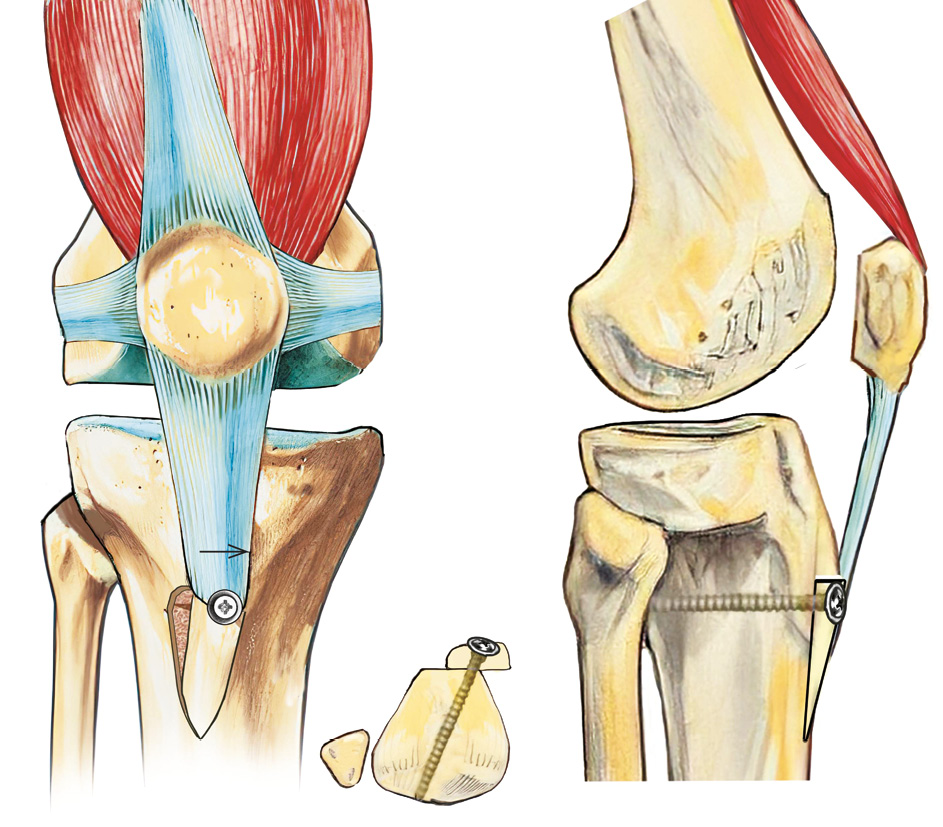

Correction of lateralization of the tibial tubercle

Surgical treatment of patients with an increased TT-TG index involves its reduction through medial transposition of the tibial tubercle along with the attachment site of the patellar ligament, according to the Elmslie-Trillat procedure [59] (see Figure 6).

Fig. 6. Scheme of medializing transposition of the tibial tuberosity according to Elmslie-Trillat

The technical simplicity and biomechanical effect of tibial tubercle transposition in cases of increased TT-TG index in correcting dysplastic patellar instability explain the popularity of this versatile surgical method in modern comprehensive treatment of this pathology. C.E. Franciozi et al. suggest that in addition to MPFL reconstruction, medialization or anteromedialization of the tibial tubercle according to Fulkerson should be performed when the TT-TG index exceeds 17 mm, achieving a tubercle position of 10-12 mm [60].

Usually, not only medialization but also medialization with distalization is performed, as excessive lateralization of the tubercle is often associated with a high-riding patella. In the context of pronounced dysplasia of types B, C, and D, the possibility of accompanying rotational and frontal deformations at the knee joint level, which can influence the true value of the TT-TG index, should be considered [48]. According to L. Jud et al., during high tibial tubercle derotational osteotomy, each degree of internal detorsion is accompanied by a decrease in the TT-TG index by 0.68 mm [61].

It is believed that additional surgical procedures, primarily tibial tubercle transposition, increase the duration of the rehabilitation period and may impact the final outcomes [39]. One challenging combination for choosing the surgical treatment approach is type D dysplasia combined with a TT-TG index greater than 20 mm [62]. L. Hiemstra et al. explain the increased risk of recurrence associated with type B and especially type D dysplasias, characterized by a pronounced trochlear bump exceeding 5 mm [63]. In such cases, trochleoplasty is recommended, and an alternative option is medialization-distalization transposition of the tibial tubercle, which allows restoring the anatomical and biomechanical relationship between the patella and the femoral trochlea without directly correcting the femur [30, 64] (see Figure 7).

Fig. 7. Scheme of distalization and medialization of the tibial tuberosity (DMTT)

Modern pathogenetically justified surgical treatment of trochlear dysplasia involves a subchondral reconstruction of the deepened femoral trochlea (trochleoplasty), which is technically complex and invasive, thus having limited indications primarily for severe dysplasia (types B and D) with an abnormal trajectory of the unstable patella. Therefore, in practice, these procedures are mostly indicated for severe dysplasia, especially in revision stabilizations of the knee joints. The main goal of such surgeries is the resection of the wedge-shaped prominence characteristic of the most severe form of trochlear dysplasia (type D), resulting in the formation of an anatomically concave surface that normalizes the patellar trajectory and stabilizes the patella [28, 64, 65] (see Figure 8).

Fig. 8. Scheme of trochleoplasty according to D. Dejour (2010)